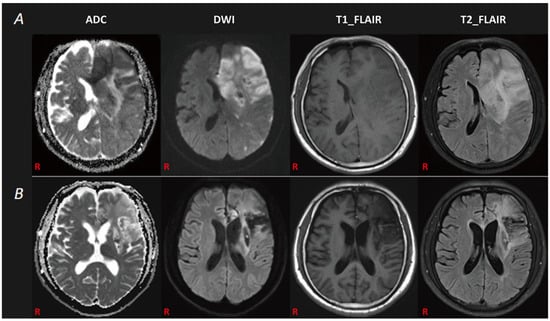

2. Case Description